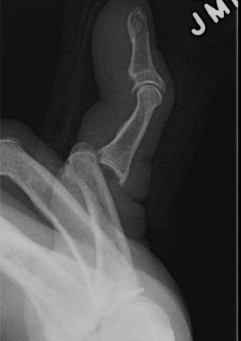

Dorsal dislocations PIPJ

Most common joint injury of the hand

- hinge joint permitting 110o ROM

- volar plate fails distally

- collateral ligaments may be intact

- may be a fracture

Mechanism

- hyperextension

- axial loading of the flexed fingertip